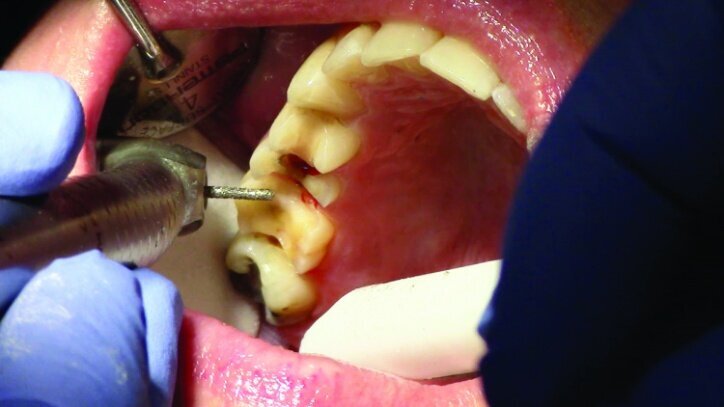

This patient presented for restorations of teeth #3 and #4 (Fig. 1a). Because of the size of the existing restorations, these teeth were diagnosed as structurally compromised (Figs. 1b, c). The prognosis without treatment was fair.

Depth guide cuts were made using a 330 bur, which has a 2 mm cutting surface (Figs. 2a–3b). This ensures 2 mm of occlusal reduction to accommodate 2 mm of material thickness on the occlusal surface of the restoration.